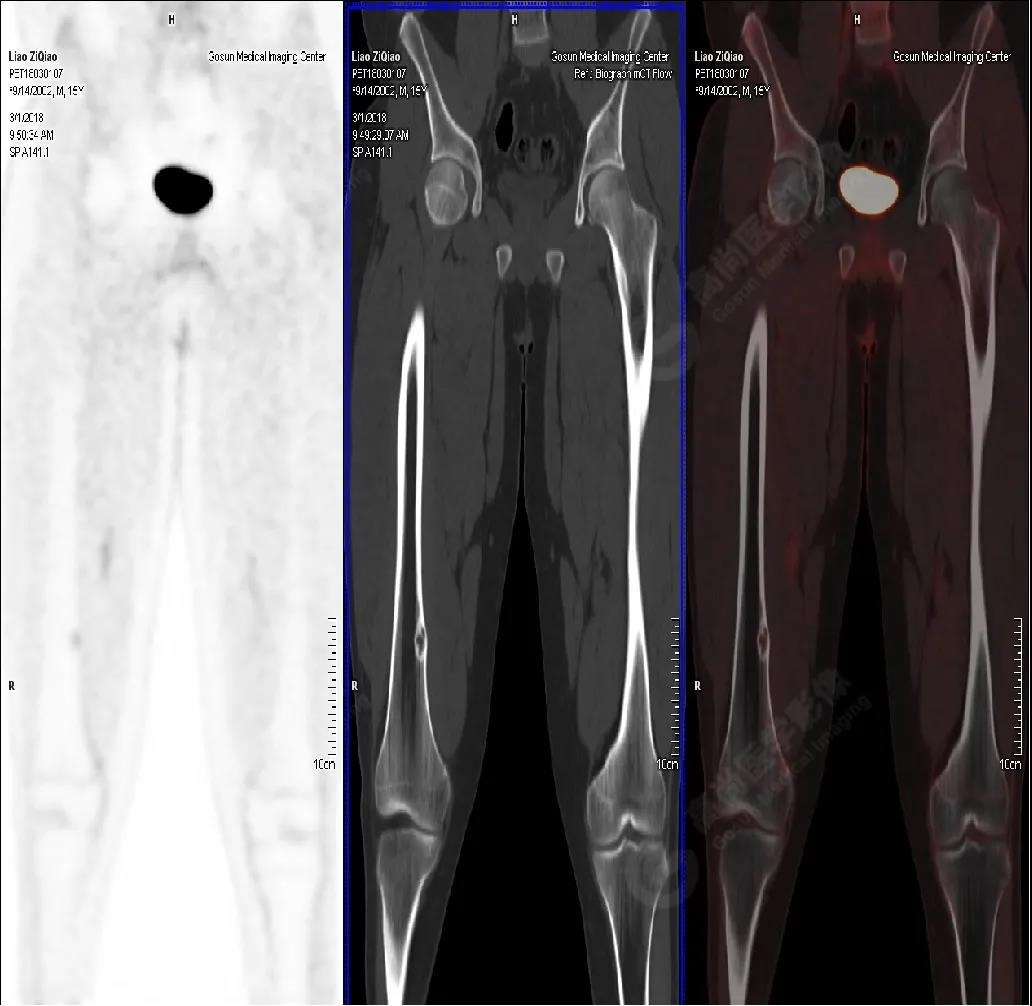

男性,15歲,右側(cè)大腿疼痛1月余,DR提示右側(cè)股骨下段囊性低密度占位。既往無外傷史、否認肝炎、結(jié)核及手術史。

PET/CT檢查

PET/CT表現(xiàn)

右側(cè)股骨下段(內(nèi)側(cè)緣)見骨皮質(zhì)局限性膨脹性破壞,突入髓腔內(nèi),邊界清楚,邊緣硬化,灶內(nèi)見纖維骨嵴,放射性攝取略增高,SUV最大值為1.4,平均值為1.3。

PET/CT診斷

右側(cè)脛骨良性骨病,以非骨化性纖維瘤可能性大。

病理診斷

隨訪結(jié)果:活檢病理確診非骨化性纖維瘤。